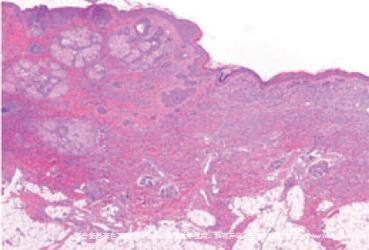

黑色素细胞痣的主要细胞学特征是黑色素细胞的巢状排列。

我们一般将黑痣分为三种,分类的原则是黑色素细胞团(细胞巢)在皮肤组织层次的位置。它们分别是

(1)交界痣

分布在表皮和真皮交界处,是黑痣的早期阶段,是境界清晰,边缘光滑的黑色或棕色斑块。随着组织成熟会逐渐落入真皮层变为皮内痣。但是脚底、手掌和外生殖器处的交界痣活性能保持到成年,有可能癌变——但是不要如临大敌,因为统计学来看,百分之八十的黑色素细胞瘤都发生在没有黑色素细胞痣的皮肤处,两者关系并没有显著联系。因此当这些部位的黑痣在短期内突然增大,且边缘不规则,颜色不均匀时,我们才需要做检查。

(2)皮内痣

交界痣脱离表皮或附属器上皮组织进入真皮,与表皮和附属器相隔一层薄薄的胶原纤维。这种痣发育成熟,表现为半球形隆起,淡褐色或皮肤色的肿物,表面光滑,而且有时中央可见毛发,也就是痣上长毛。临床上目前未见报道皮内痣恶变,因此如果你的痣是这种,请不要忧虑恶变的问题,当然如果痣太大影响美观,进行去除也是可行的。

(3)混合痣

顾名思义,是兼顾两种痣特点的痣,是隆出皮面的黑褐色丘疹、斑丘疹,界限清晰,同样常常有毛发[1]。